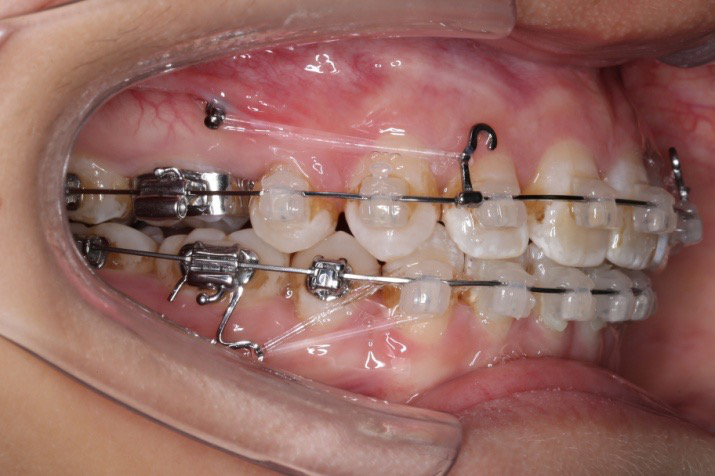

2016.10.31  初戴,0.013cu-niti2017.1.13  上颌加TPA,U56间斜形植入韩国庆北1312-08种植钉,上下0.16cu-niti

2017.02.16  上下0.014*25 cu-niti,50g 拉尖牙远中

2017.04.28

2017.04.28  上0.016*25ss 13、23近远中约5度 v形曲,下0.017*25ss

2017.05.26  磨牙近中倾斜,下颌36、46加power arm

2017.07.25

2017.07.25  上前牙加颈部弹力线

2017.10.07  继续关间隙,下颌使用水平关间隙

下颌磨牙通过powerarm直立效果明显,下颌整平效果明显